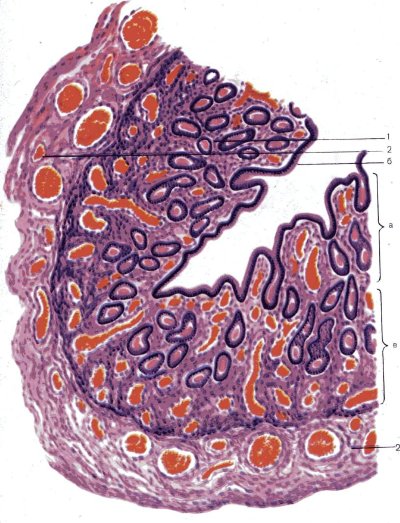

Внутри мы видим реснитчатый эпителий (синий внутренний контур) — он частично реснитчатый —реснички где-то есть, где-то их нету. Как это часто в эпителиальной призматической однослойной части бывает — реснички обеспечивают движение яйцеклетки (против тока сперматозоидов). Клетки с синим контуром — это железы, которые будут выделять потом гликоген и все питательные веществ до тех пор, пока не образуется плацента.

НО! Слизистая матки, ЭНДОМЕТРИЙ, служит обратному эффекту — напитать зародыш как можно более качественно, пока не образуется полноценная плацента, через которую уже будет происходить обмен веществ между организмом матери и ребенка при помощи образования совместной системы кровообращения, где плацента является своеобразным трансформатором и переключателем между мамой и дитем.